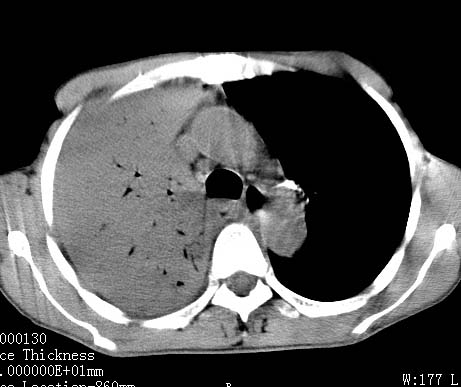

病人女 60岁 咳嗽 气促十余天,大叶性肺炎.

右肺上下叶均见 大片状密度增高影,边界清晰,其内可见支气管充气征,气管支气管通畅。纵膈略向右移位,其内无肿大淋巴结影。首先考虑炎性病变。不排除一些特异性的炎症。不知道发烧吗??wbc高吗??建议治疗后复查!!